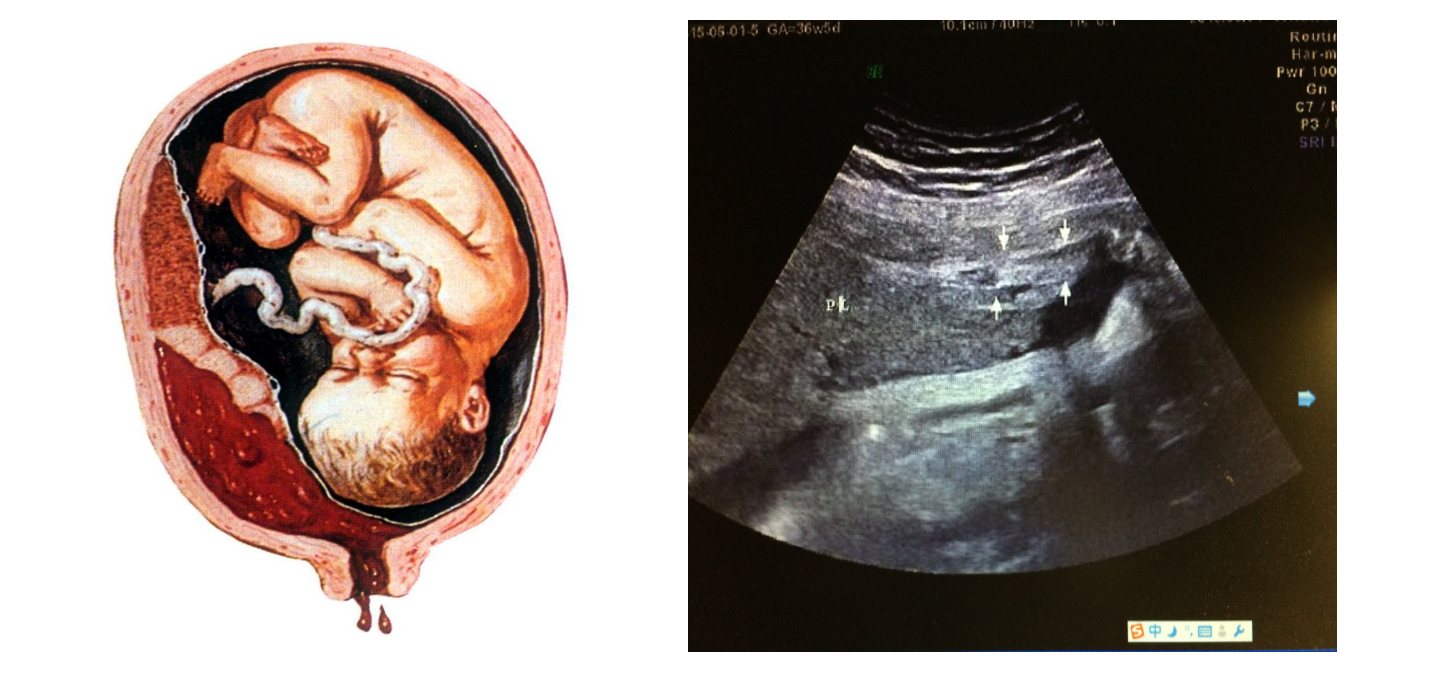

• 4.5 胎盘异常声像图

胎盘异常声像图